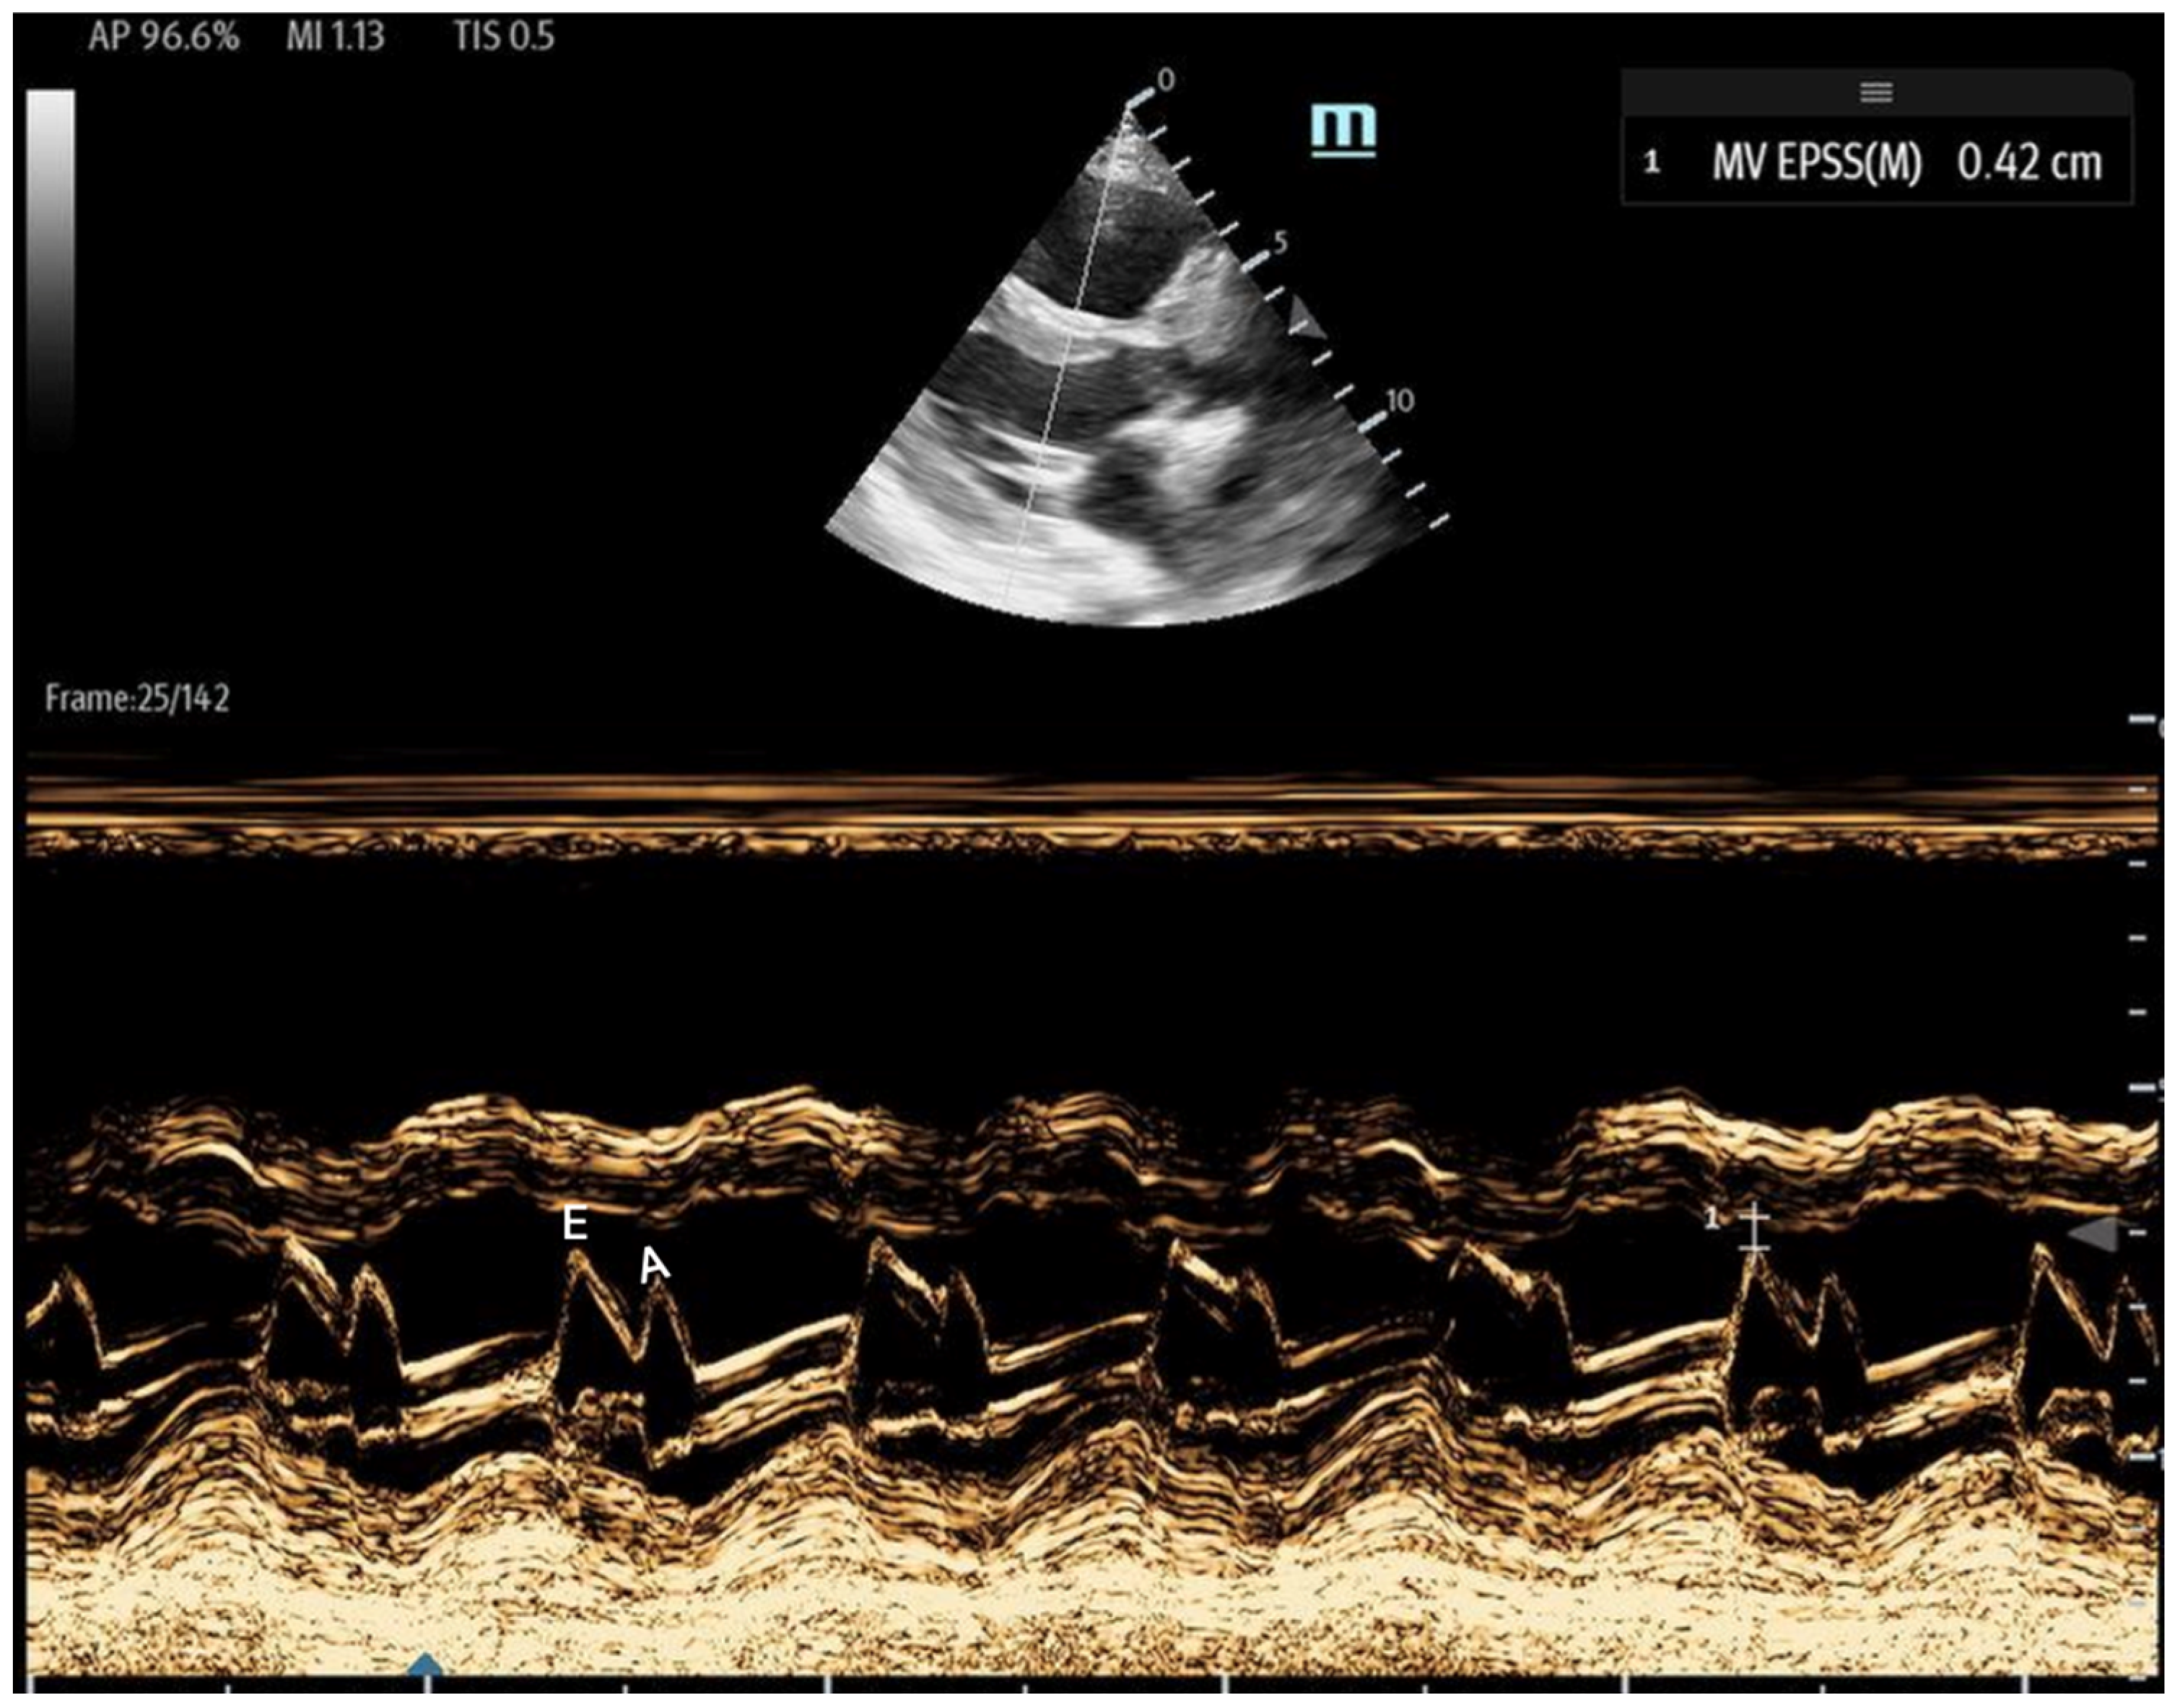

- 1E-point Septal Separation (EPSS): Obtained in the parasternal long-axis (PLAX) view, EPSS quantifies the distance between the anterior mitral valve leaflet tip and the interventricular septum (Figure 11). An EPSS greater than 1 cm may indicate a reduced LVEF of less than 40%, with a sensitivity of 69% and specificity of 91% [54]. This method requires only brief bedside training [55]. However, EPSS may not accurately reflect cardiac function in certain patients. In those with valvular pathologies (e.g., mitral stenosis/prosthesis or aortic regurgitation), abnormal valve or leaflet movement can lead to falsely high EPSS measurements despite normal LVEF. Septal hypertrophy may also underestimate EPSS. Lastly, in atrial fibrillation, the lack of coordinated atrial contractions necessitates multiple measurements for reliable assessments [56].

Figure 11. The parasternal long-axis view with the M-mode shows the EPSS measurement, which is the minimal distance between the E wave (initial and maximal opening of the mitral for the passive filling of LV) and the septum. The E wave is followed by the A wave, which is smaller and corresponds to left atrial contraction. - Fractional Shortening (FS): Obtained in the PLAX view, FS measures the left ventricular (LV) end-systolic and end-diastolic diameters. It evaluates the percentage change in LV diameter between diastole and systole, which is calculated as:FS serves as an estimate of how effectively the LV contracts and can be used as a surrogate for LVEF. However, it may be falsely low in areas of wall motion abnormalities and is highly influenced by preload and afterload. Additionally, FS has been shown to underestimate LVEF in patients with concentric left ventricular hypertrophy [57,58].